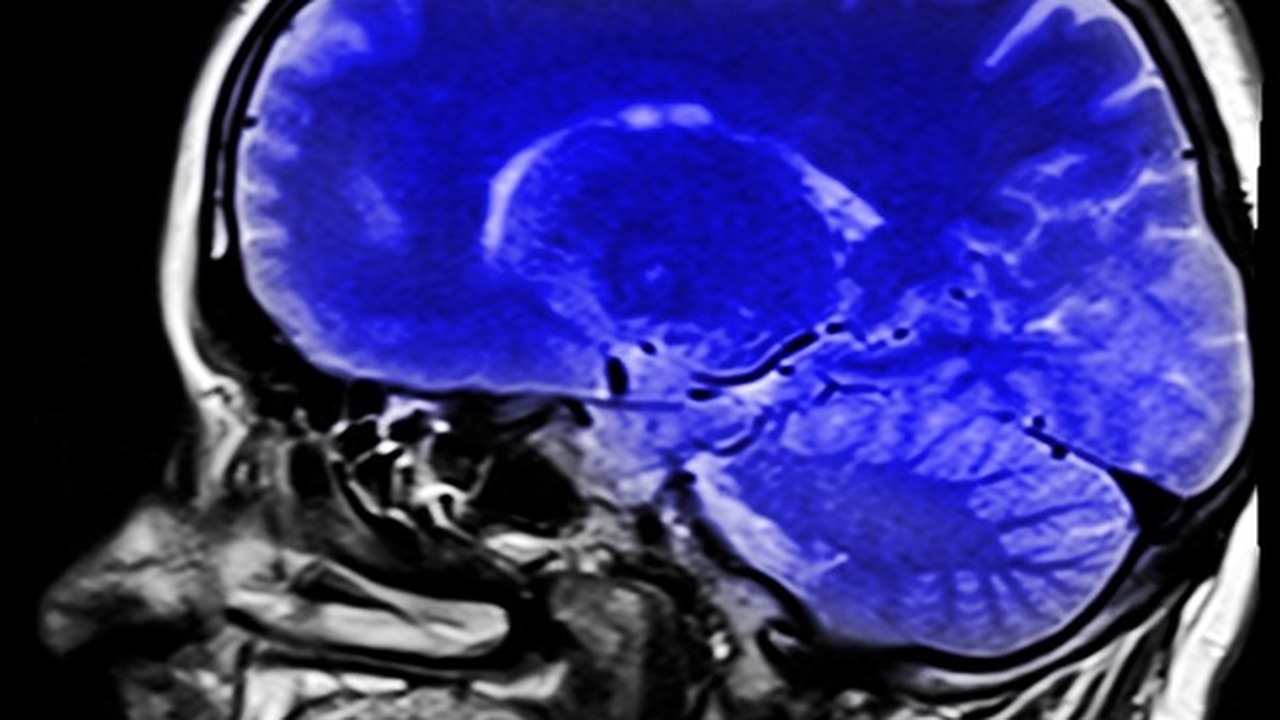

Исследователи обнаружили тревожную связь между некоторыми распространенными инфекционными заболеваниями и ускоренным снижением когнитивных функций у пожилых людей. Согласно их выводам, перенесенные инфекции могут способствовать уменьшению объема мозга, особенно в тех его отделах, которые отвечают за формирование и хранение воспоминаний.

В ходе масштабного анализа данных, охватившего почти тысячу участников Балтиморского исследования старения, ученые сопоставили информацию об объеме мозга с историей перенесенных инфекций. Результаты показали, что шесть типов инфекций оказывают заметное негативное влияние на структуру мозга, приводя к его уменьшению. В этот список вошли такие заболевания, как грипп, различные герпесвирусы, респираторные и кожные инфекции, а также другие вирусные патогены.

Особое внимание исследователи уделили гриппу и инфекциям, вызванным вирусами герпеса. Было установлено, что именно эти заболевания наиболее тесно связаны с сокращением объема височной доли мозга – ключевой области, играющей центральную роль в процессах памяти.